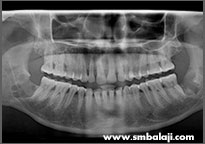

CASE III

X-ray showing teeth impacted in the lower right jaw region

Impacted teeth surgically removed